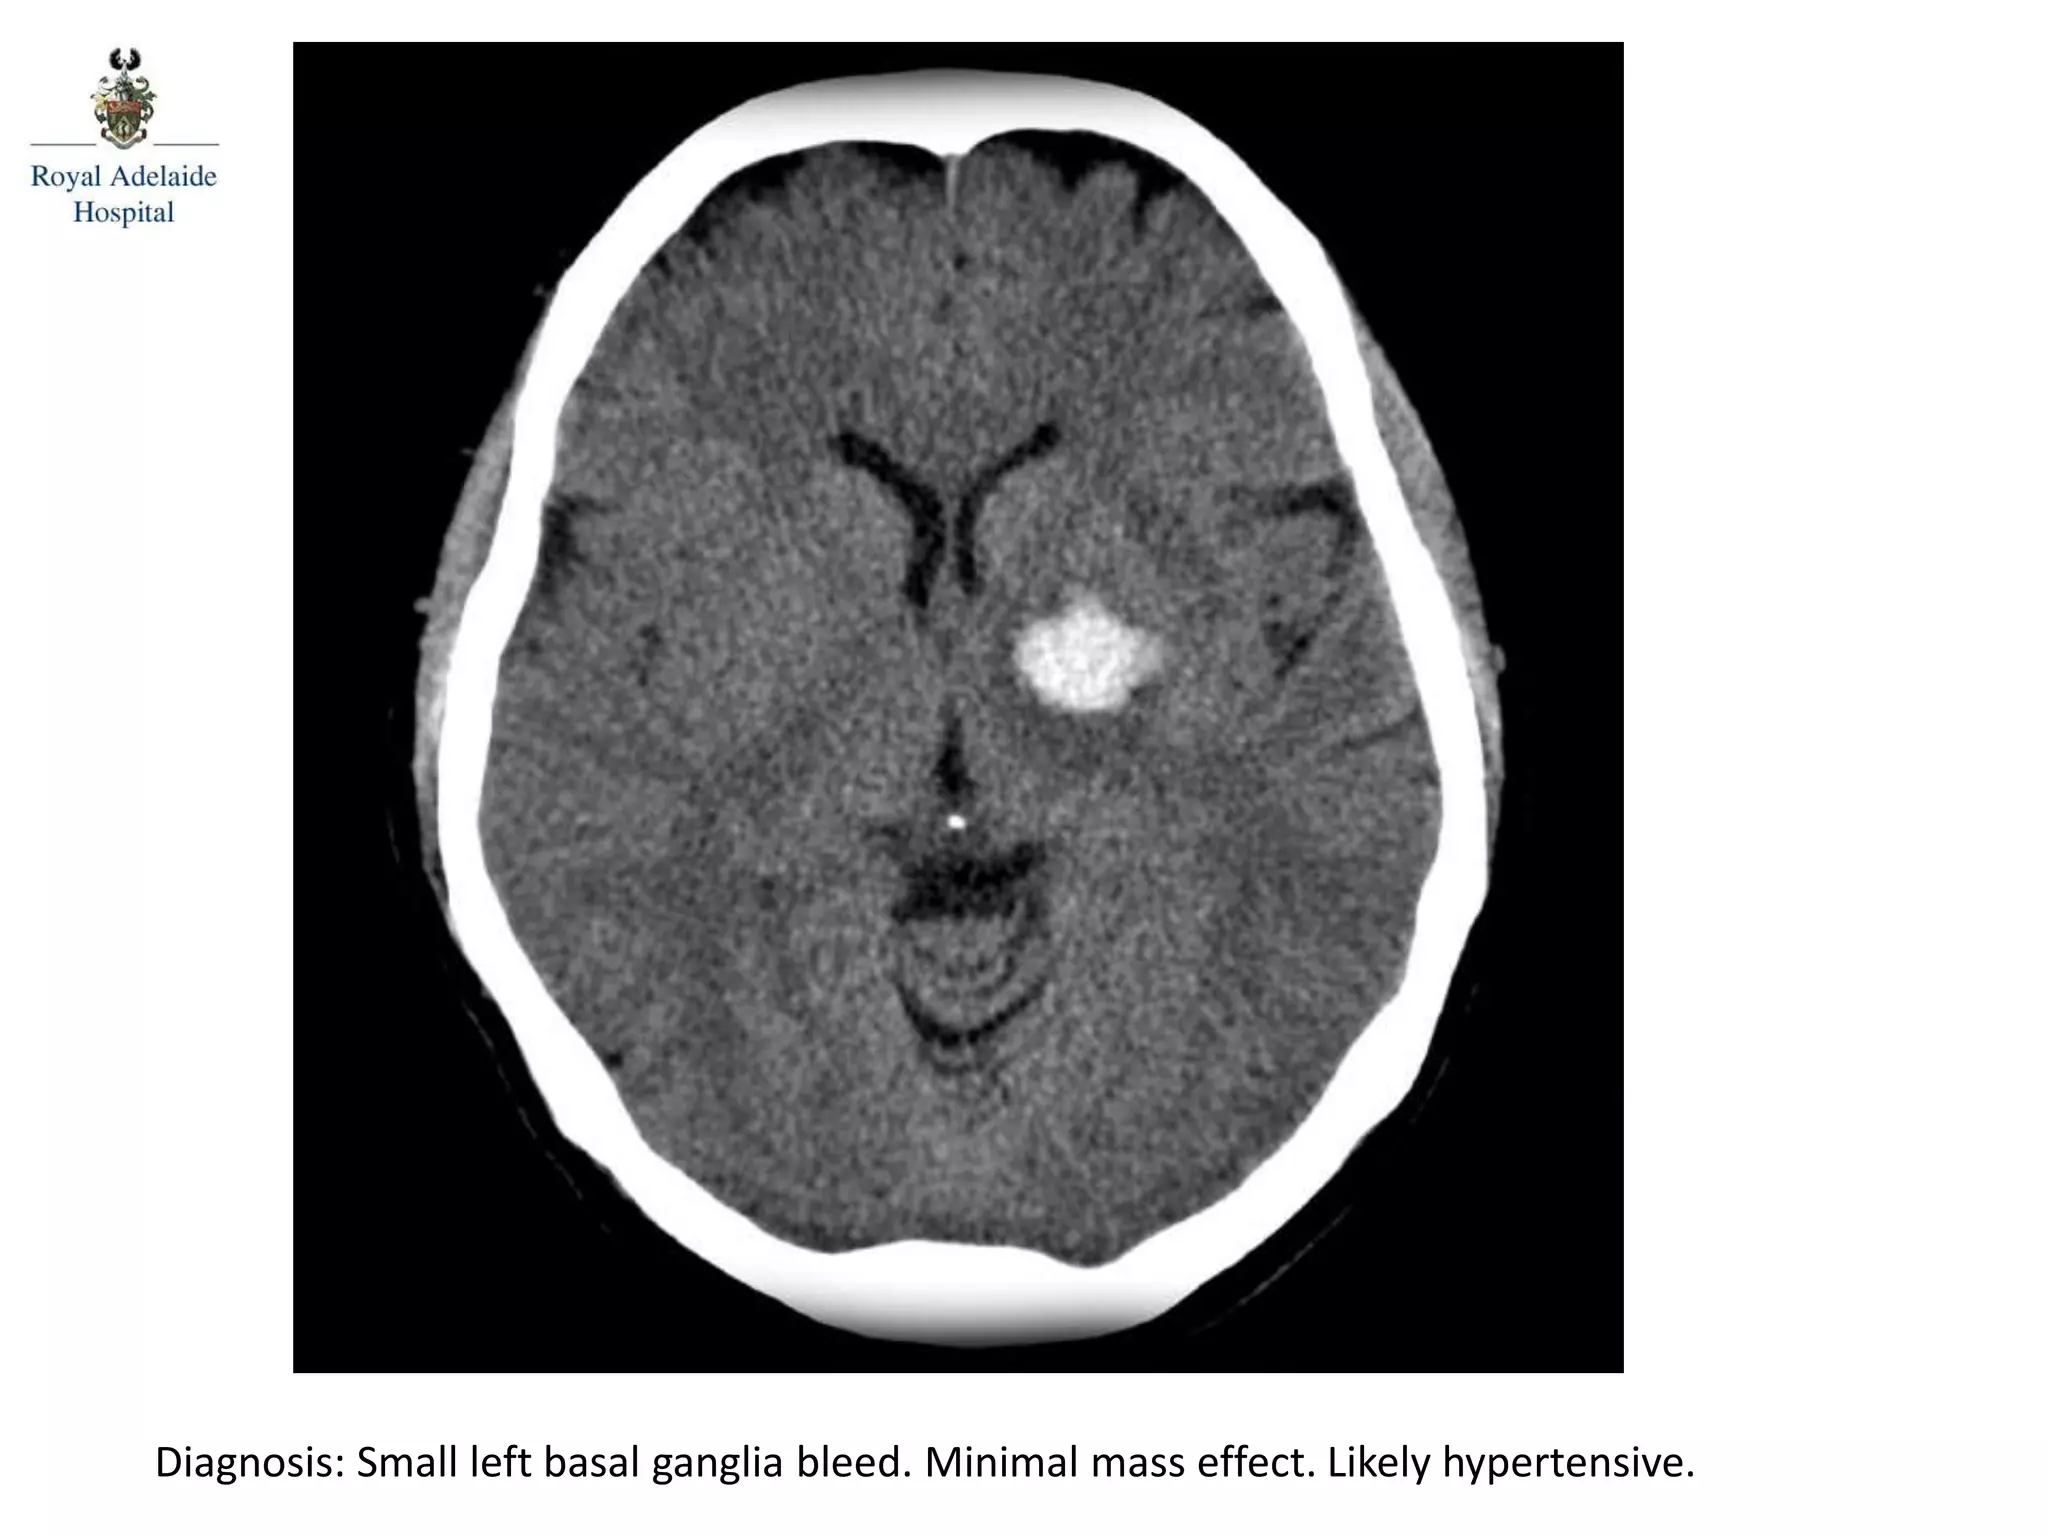

The document outlines multiple diagnoses from head CT cases, including small left basal ganglia bleed likely due to hypertension, various types of subdural and subarachnoid hemorrhages, and evidence of hydrocephalus. It details traumatic origins of some hemorrhages and notes obstructing masses and atrophic changes. Overall, there are significant findings indicating complications related to cerebral hemorrhages and ventricular enlargement.